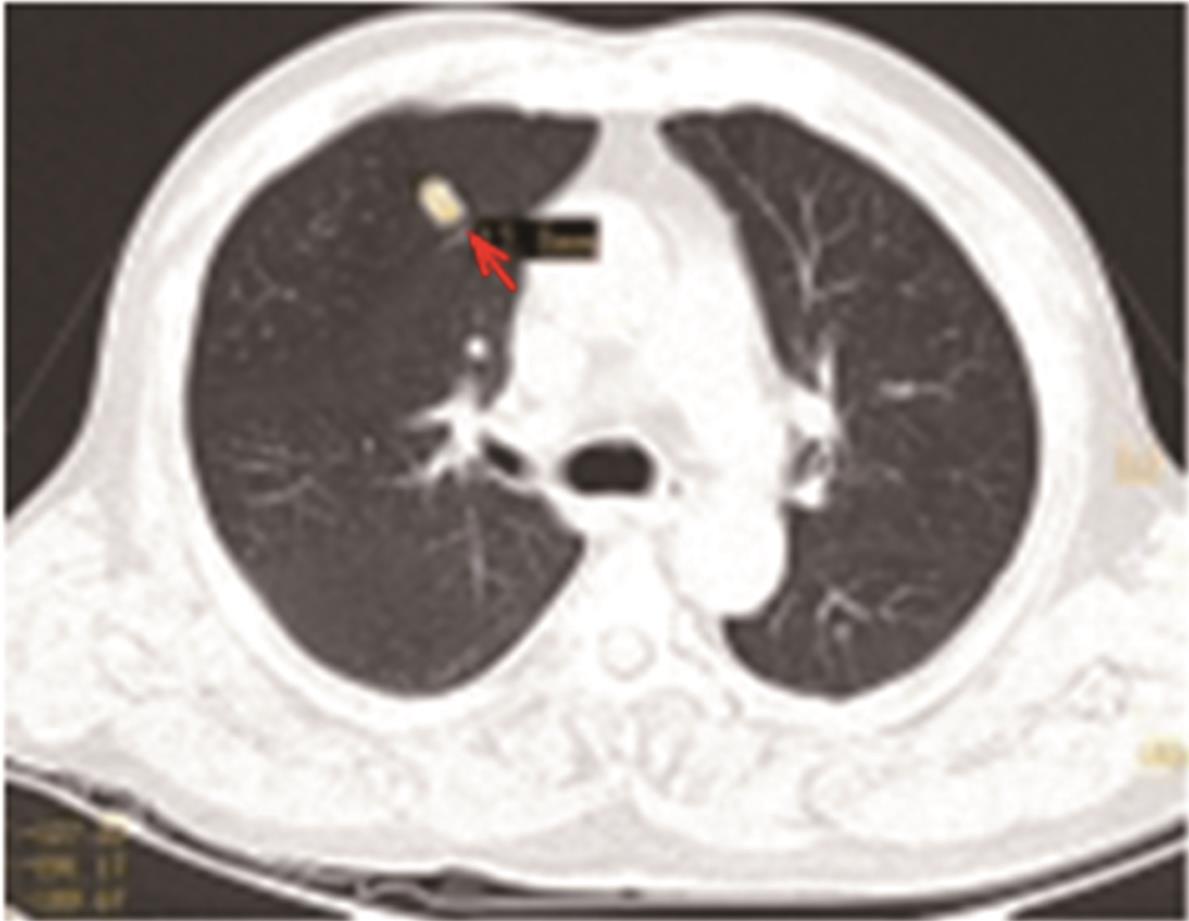

• 转移性上尿路上皮癌在维迪西妥单抗联合替雷利珠单抗新辅助治疗后行根治性肾盂癌切除术1例报道

2023, 48(8):1005-1008. DOI: 10.13406/j.cnki.cyxb.003299

摘要 (52) HTML (36) PDF 2.16 M (1929) 评论 (0) 收藏